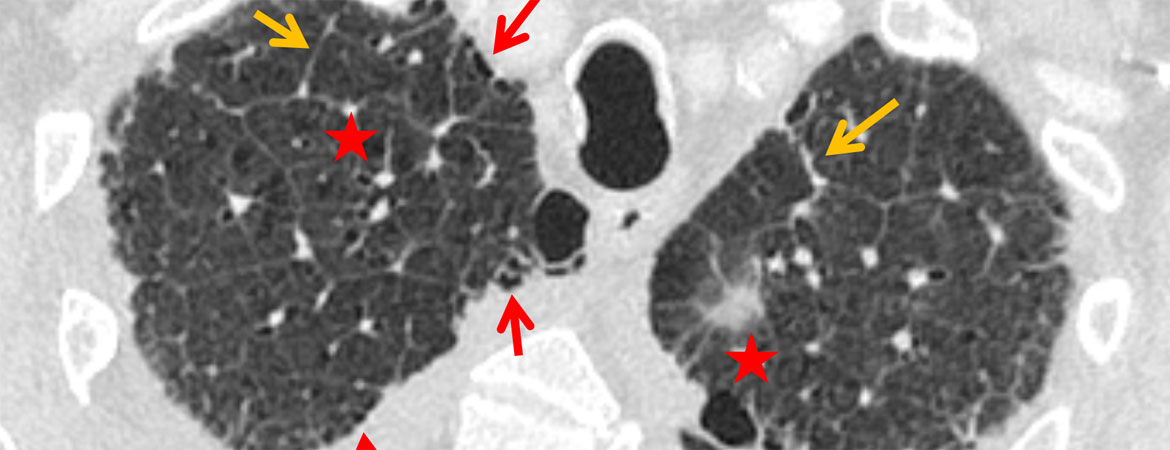

Laura I. Loebelenz, Lukas Ebner, Verena C. Obmann, Adrian T. Huber, Andreas Christe (Author) Kerley B lines in the lung apex – a distinct CT sign for pulmonary congestion Fulltext PDF Fulltext HTML